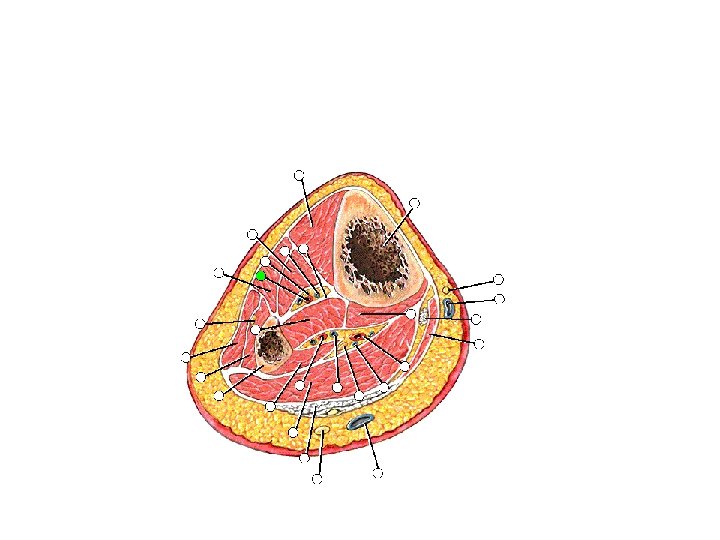

Posterior Leg Muscles • Which nerve? • Superficial posterior muscles – Gastrocnemius muscle – Soleus muscle – Plantaris muscle • Deep posterior muscles – – Popliteus muscle Flexor digitorum longus muscle Flexor hallucis longus muscle Tibialis posterior muscle